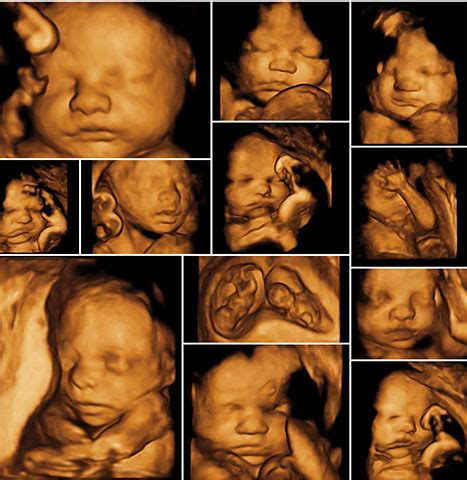

Trojrozmerný (3D) ultrazvuk sa objavil už pred 10 rokmi ako nová možnosť ultrazvukového zobrazenia. 4D zobrazenie predstavuje najnovšiu technológiu, pri ktorej rýchlo snímané trojrozmerné obrázky umožňujú vyšetrenie plodu, alebo jeho orgánov plasticky, v reálnom čase. Až v poslednej dobe bolo možné vytvoriť toto zobrazenie pomocou moderných počítačových technológií. Tieto sa využívajú na spracovanie veľkých objemov dát, okrem iného aj na tzv. 4D zobrazenie.

Toto vyšetrenie je možné uskutočniť kedykoľvek, optimálne zobrazenie plodu je však medzi 18. - 26. týždňom tehotnosti. Tento spôsob zobrazí aj detaily kostí, ktoré nie je možné zaznamenať pri klasickom ultrazvukovom zobrazení. Tento spôsob zobrazenia predstavuje unikátnu možnosť zobrazenia celého srdca a jeho činnosť v priebehu jedného srdcového cyklu. Dĺžka trvania vyšetrenia sa nelíši od bežného ultrazvukového vyšetrenia, nakoľko výkon prístroja umožňuje spracovanie všetkých dát v reálnom čase.